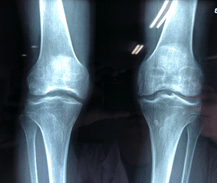

在家人的陪同下我去臺大醫院做了檢查,顯示:『膝軟骨磨損,膝關節退變、骨質增生』關節腔內有積水,然後醫院就給我抽了積液,還給打了玻璃酸鈉,也開了一大堆的口服藥,一系列止疼藥,回家後的一周時間裡,確實還可以,走路都不影響,可是後來又復發了。

慢慢演變成『坐久了起來關節僵硬,上下樓很費勁,用不上力,蹲也蹲不下去,蹲下就起不來』心想,這下糟了,不會要殘廢了吧,就又去醫院問了專家,專家說"你的問題比較複雜,需要做關節置換才可以。我聽完嚇了一跳,好好的腿,置換了還是我的膝蓋嗎?我內心帶著疑惑和恐懼就回家了,徵求家人的意見,可單是手術費就要10多萬,並且手術風險太大.最後決定還是保守治療吧,然後我就踏上了尋求良藥的艱辛之路,一直堅持但是沒有好轉。

②如果您是“膝關節骨質增生、骨刺,滑膜炎,膝軟骨磨損,髕骨軟化",導致不能正常勞動,不能正常工作,無法正常生活,甚至面臨手術或者癱瘓的人。